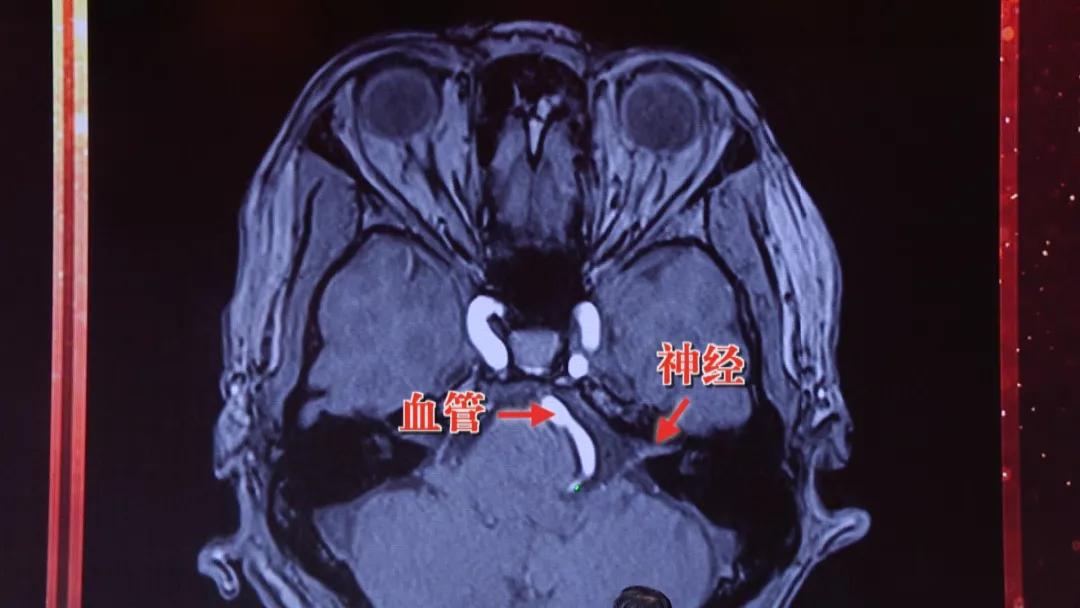

通过磁共振检查,如果有特殊的高血压,那么可以发现血管压到了神经,而普通高血压没有这种发现;另外特殊高血压伴随表现为 眼皮跳、脸疼 。

造成这种特殊高血压的原因,其实是 脑子里的血管压迫到了迷走神经区域 ,才会出现久治不愈的高血压,如果同时压迫到 面神经 ,就会出现 眼皮跳 等高血压的伴随症状。